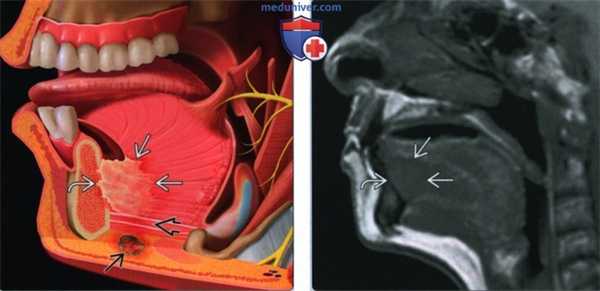

(Слева) На рисунке показано наиболее частое расположение ПКР дна полости рта: в пределах 2 см от средней линии в передних отделах. При анализе изображений важно оценить распространение опухоли каудально с инвазией подбородочно-язычной и челюстно-подъязычной мышц, кзади по направлению к корню языка, и кпереди или латерально с инвазией нижней челюсти. С этой целью может потребоваться и МРТ, и КТ. Другой целью методов визуализации является оценка вторичного поражения лимфатических узлов.

(Справа) При МРТ Т1ВИ в сагиттальной проекции визуализируется объемное образование с сигналом низкой интенсивности по сравнению с мышцами языка, прилежащее вплотную к нижней челюсти по средней линии.